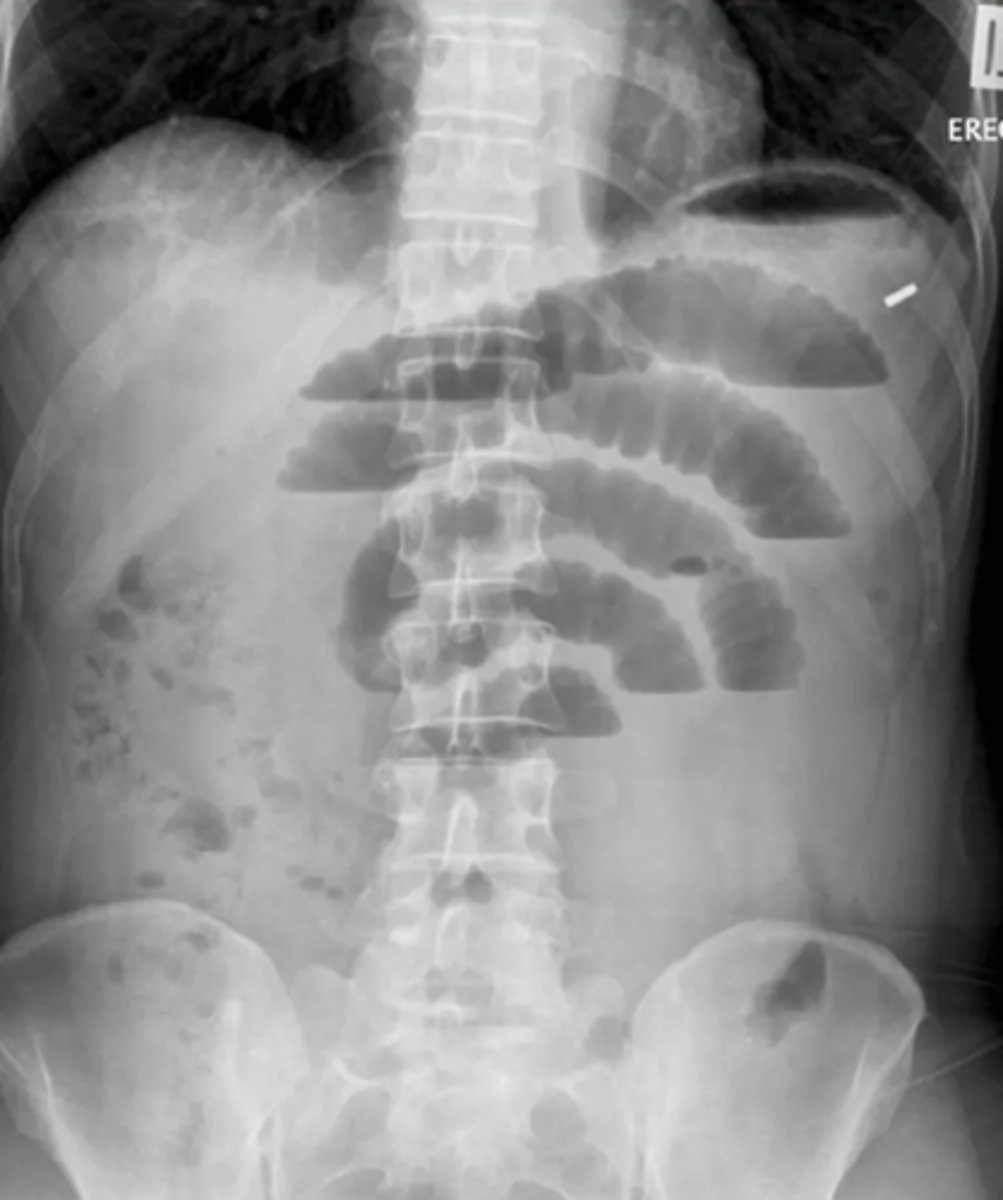

dilated loops of bowel air fluid levels

dilated loops of bowel

small bowel obstruction usually starts in the ______

LUQ

causes of SBO

post-operative adhesions, malignancy, hernias, gallstone ileus, intussusception, IBD